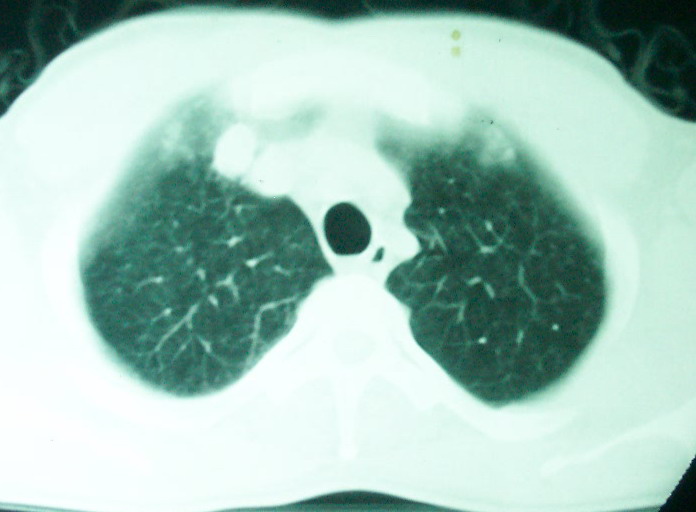

m      37y      发热   咳脓痰月余      ct肺脓肿但住院抗炎治疗后双肺内结节不知该如何解释

治疗后见左肺下野病灶较前缩小但双肺内结节影似无变化请较各位老师该如何下结论    治疗前wbc14.5 治疗后wbc 11.0

血源性肺脓肿,一般由原发感染灶引起脓毒败血症,在肺部形成小脓肿,病变变化快,容易形成肺气囊,脓气胸,主要与转移瘤鉴别,通过临床病史可分

结合临床发热,咳痰考虑为血源性肺脓肿,不过双肺结节又在肺的边缘,还是小心一点,抗炎后复查吧

除了肺内多发结节和左肺下叶的浓疡病灶,还应注意满肺散在的小结节影,还有右上肺前段支气管内膜不光整这些细节,结合病史,肺内多发结节应考虑结核性肉芽!